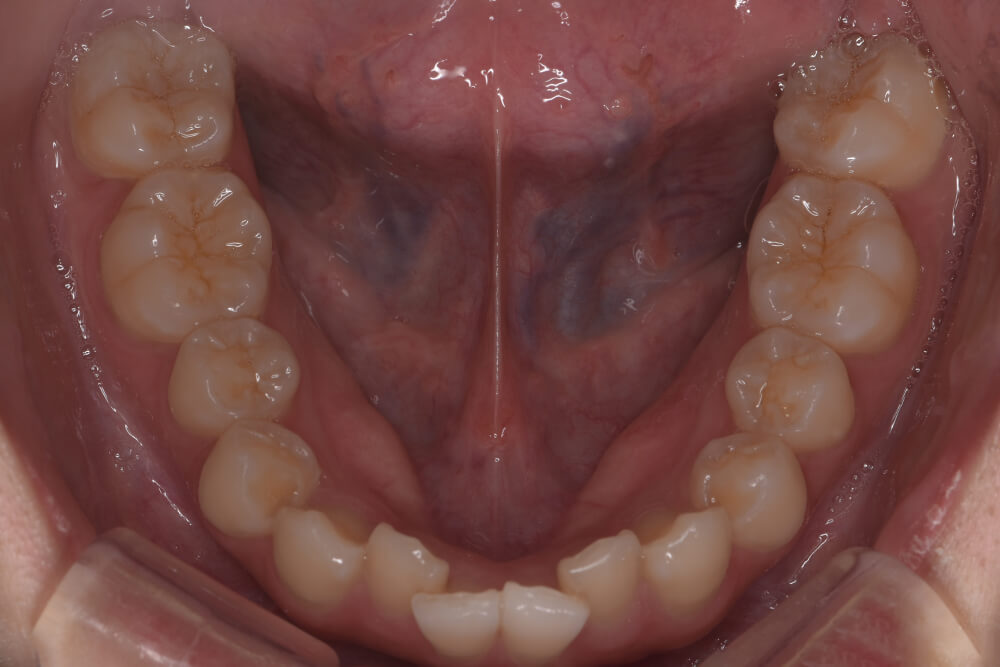

CASE05

Before

After

| コース | 7回コース+追加1回 |

|---|---|

| IPR | 2回 |

| 治療期間 | 10ヶ月 |

| 治療費 | 300,300円 |

| 年齢・性別 | 20代男性 |